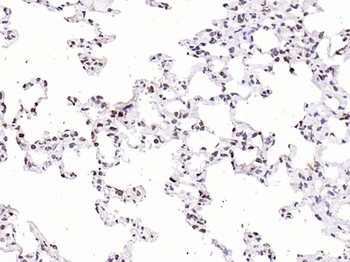

CDKN1A Antibody

Catalog Number: orb682382

| Description | CDKN1A Antibody |

| Target | CDKN1A |

| UniProt ID | P38936 |